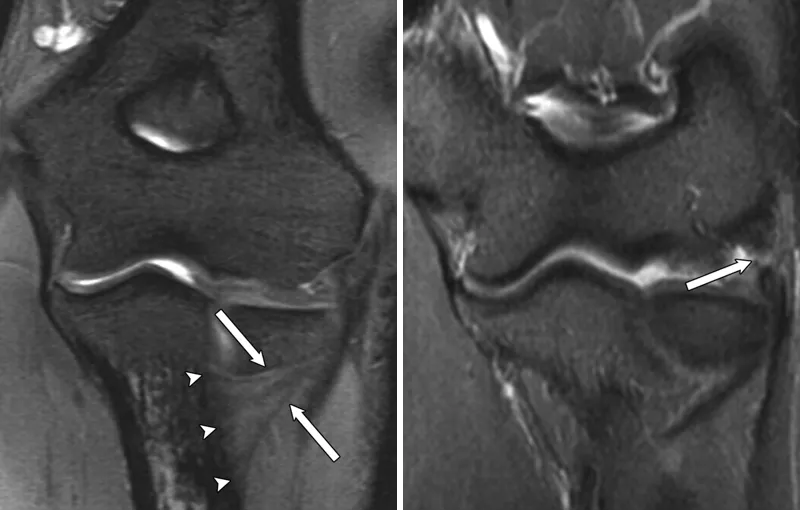

(a)33 岁女性受试者的矢状位 T2 加权磁共振成像,以及(b)对应的示意图,清晰显示出后外侧滑膜皱襞的前后径(白色箭头所示)与头尾径(黑色箭头所示)。图中 AM 代表肘肌。

(c)与图 a 相同的磁共振影像,以及(d)对应的示意图,显示出肱骨小头的假性缺损(箭头所示),及其与后外侧滑膜皱襞的密切关联。图中 AM 代表肘肌。